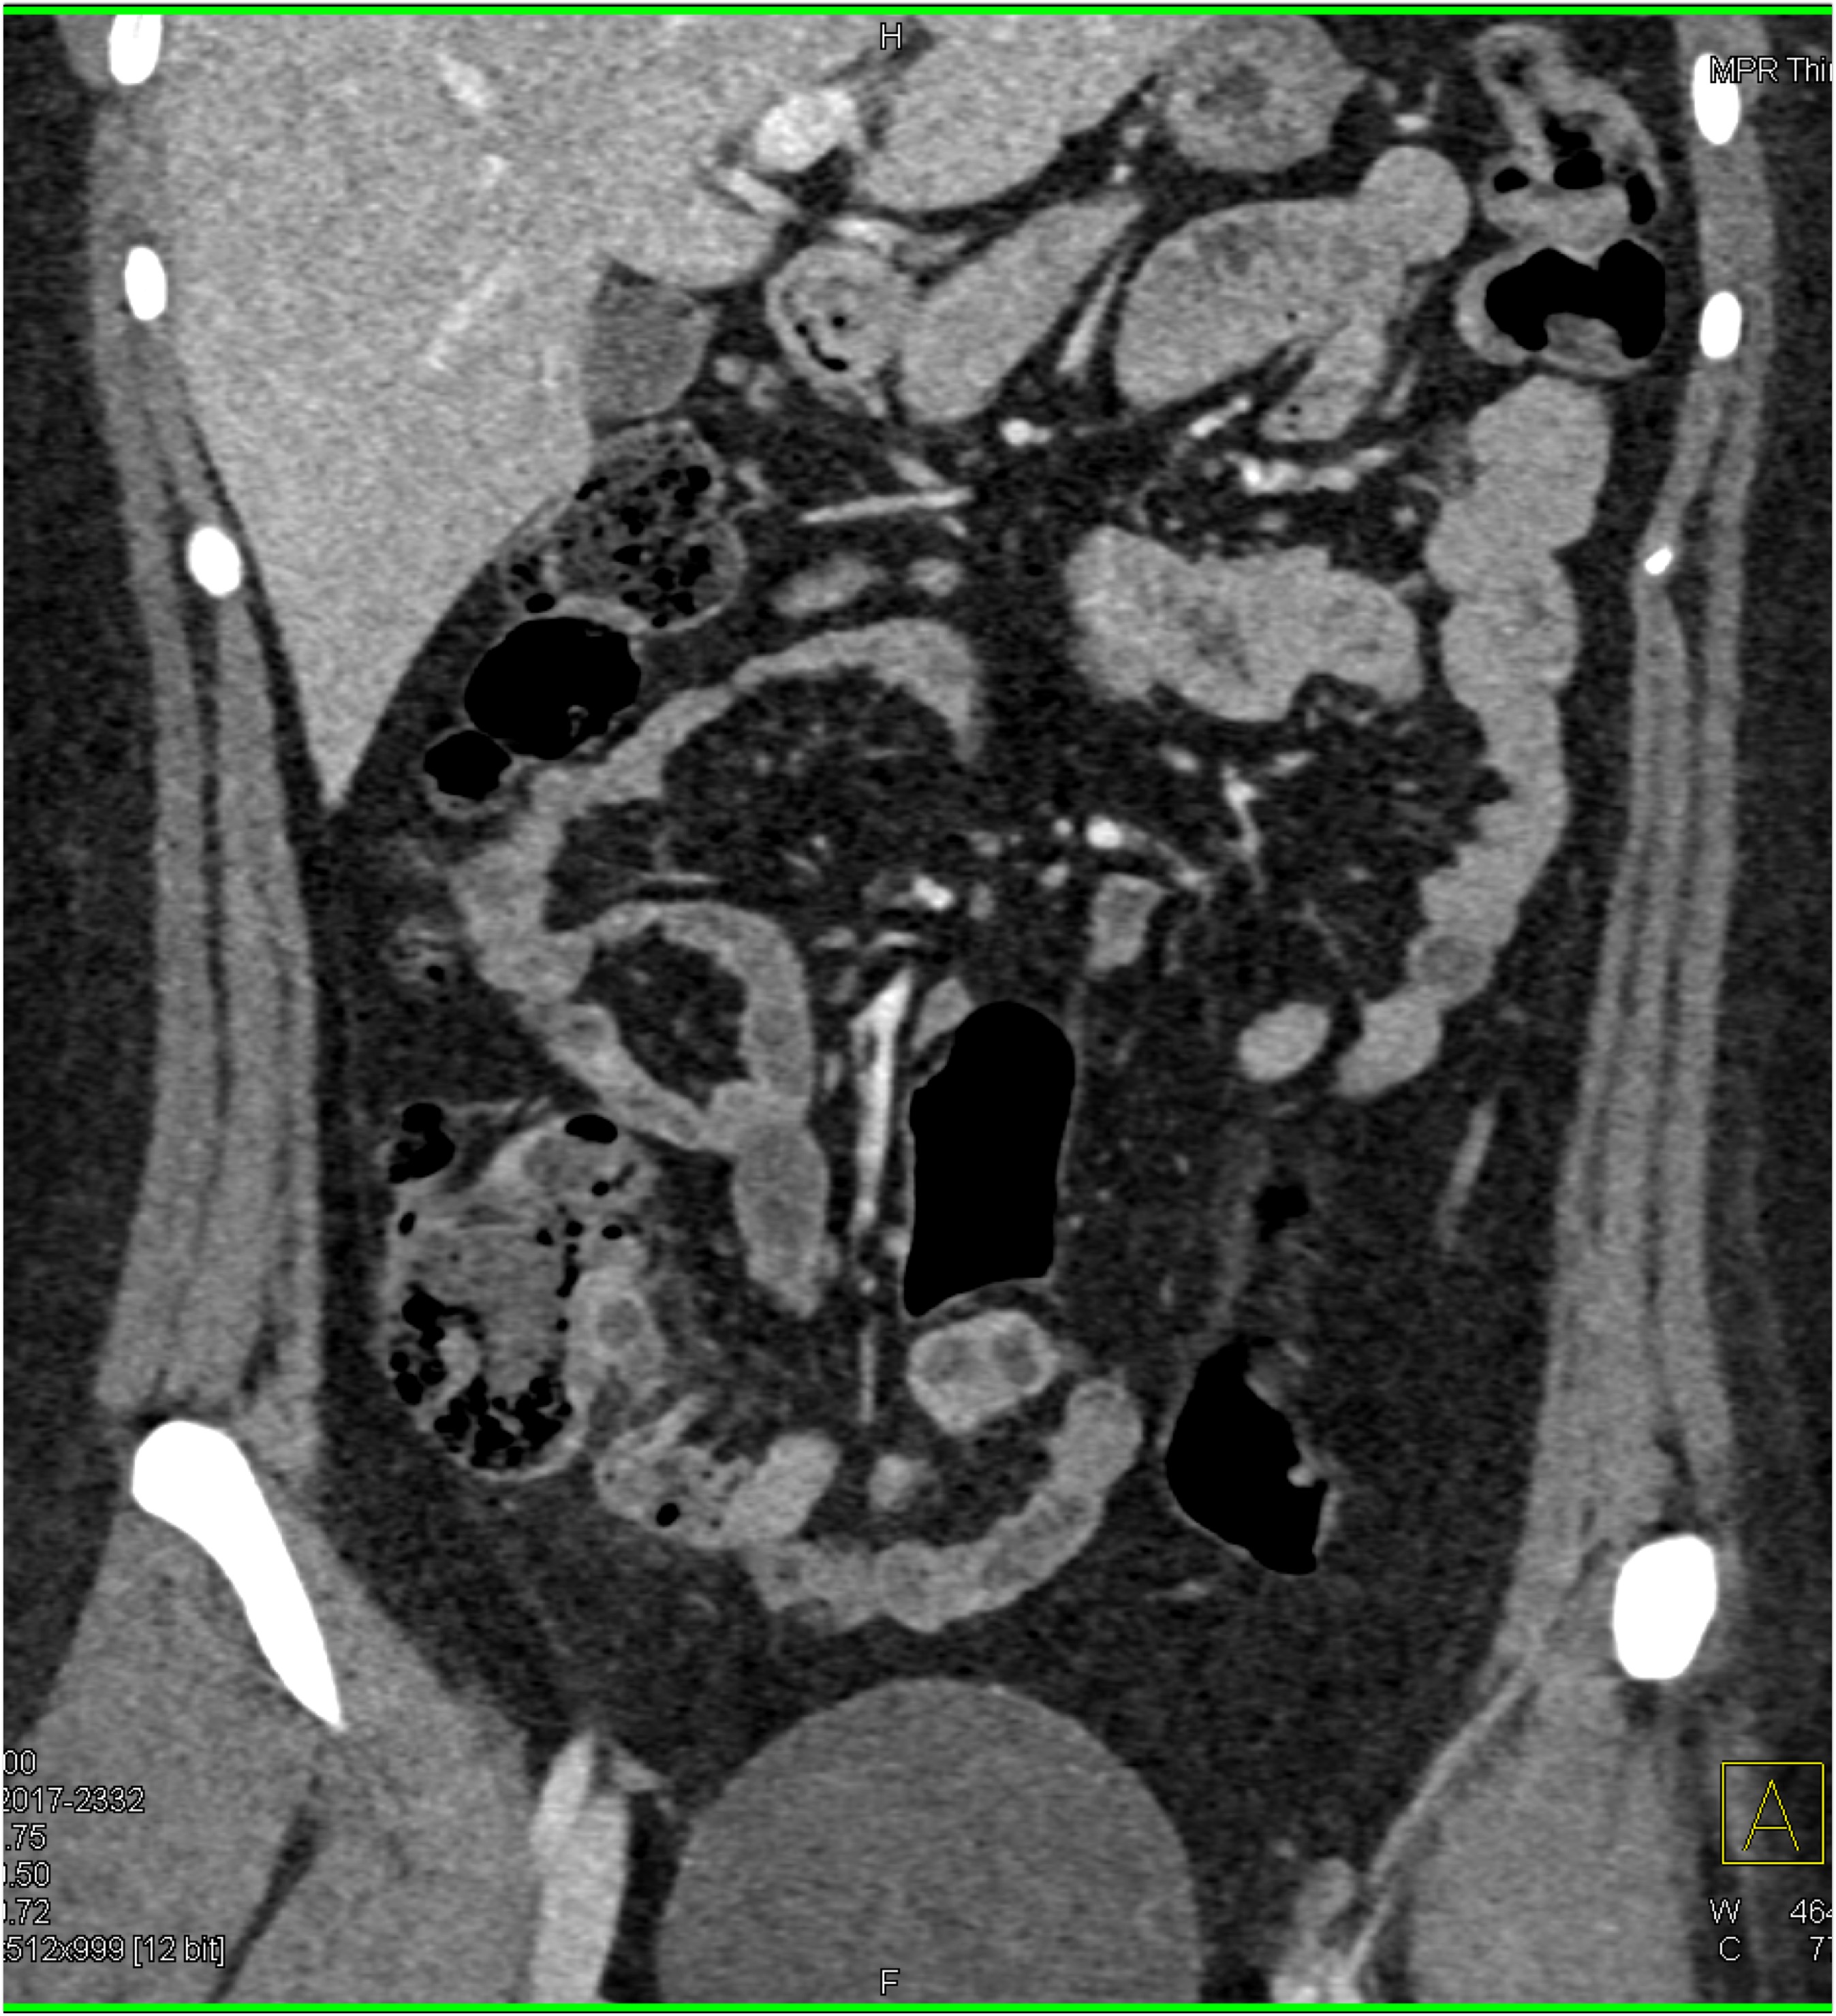

5) In this patient with Crohn’s disease and abdominal pain the critical CT finding is

stricture of colon

bowel wall thickening

active GI bleed

superimposed colon cancer